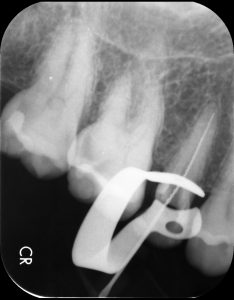

治療中

根管治療は歯の上から見ながら治療を行いますが、神経の管は髪の毛ほどの細さしかありません。保険診療の根管治療では肉眼で細い根管を治療しますが、管の先を見ながら治療することはほぼ不可能です。そのため、神経や感染の取り残しがあることで治療をしても痛みや腫れがなくならない、数年後に痛みが出る原因となります。当院ではマイクロスコープを使用し、管の先をしっかりと確認しながら治療を行います。また、治療中にレントゲン撮影を行い、根っこの先まで治療器具が到達しているか確認します。